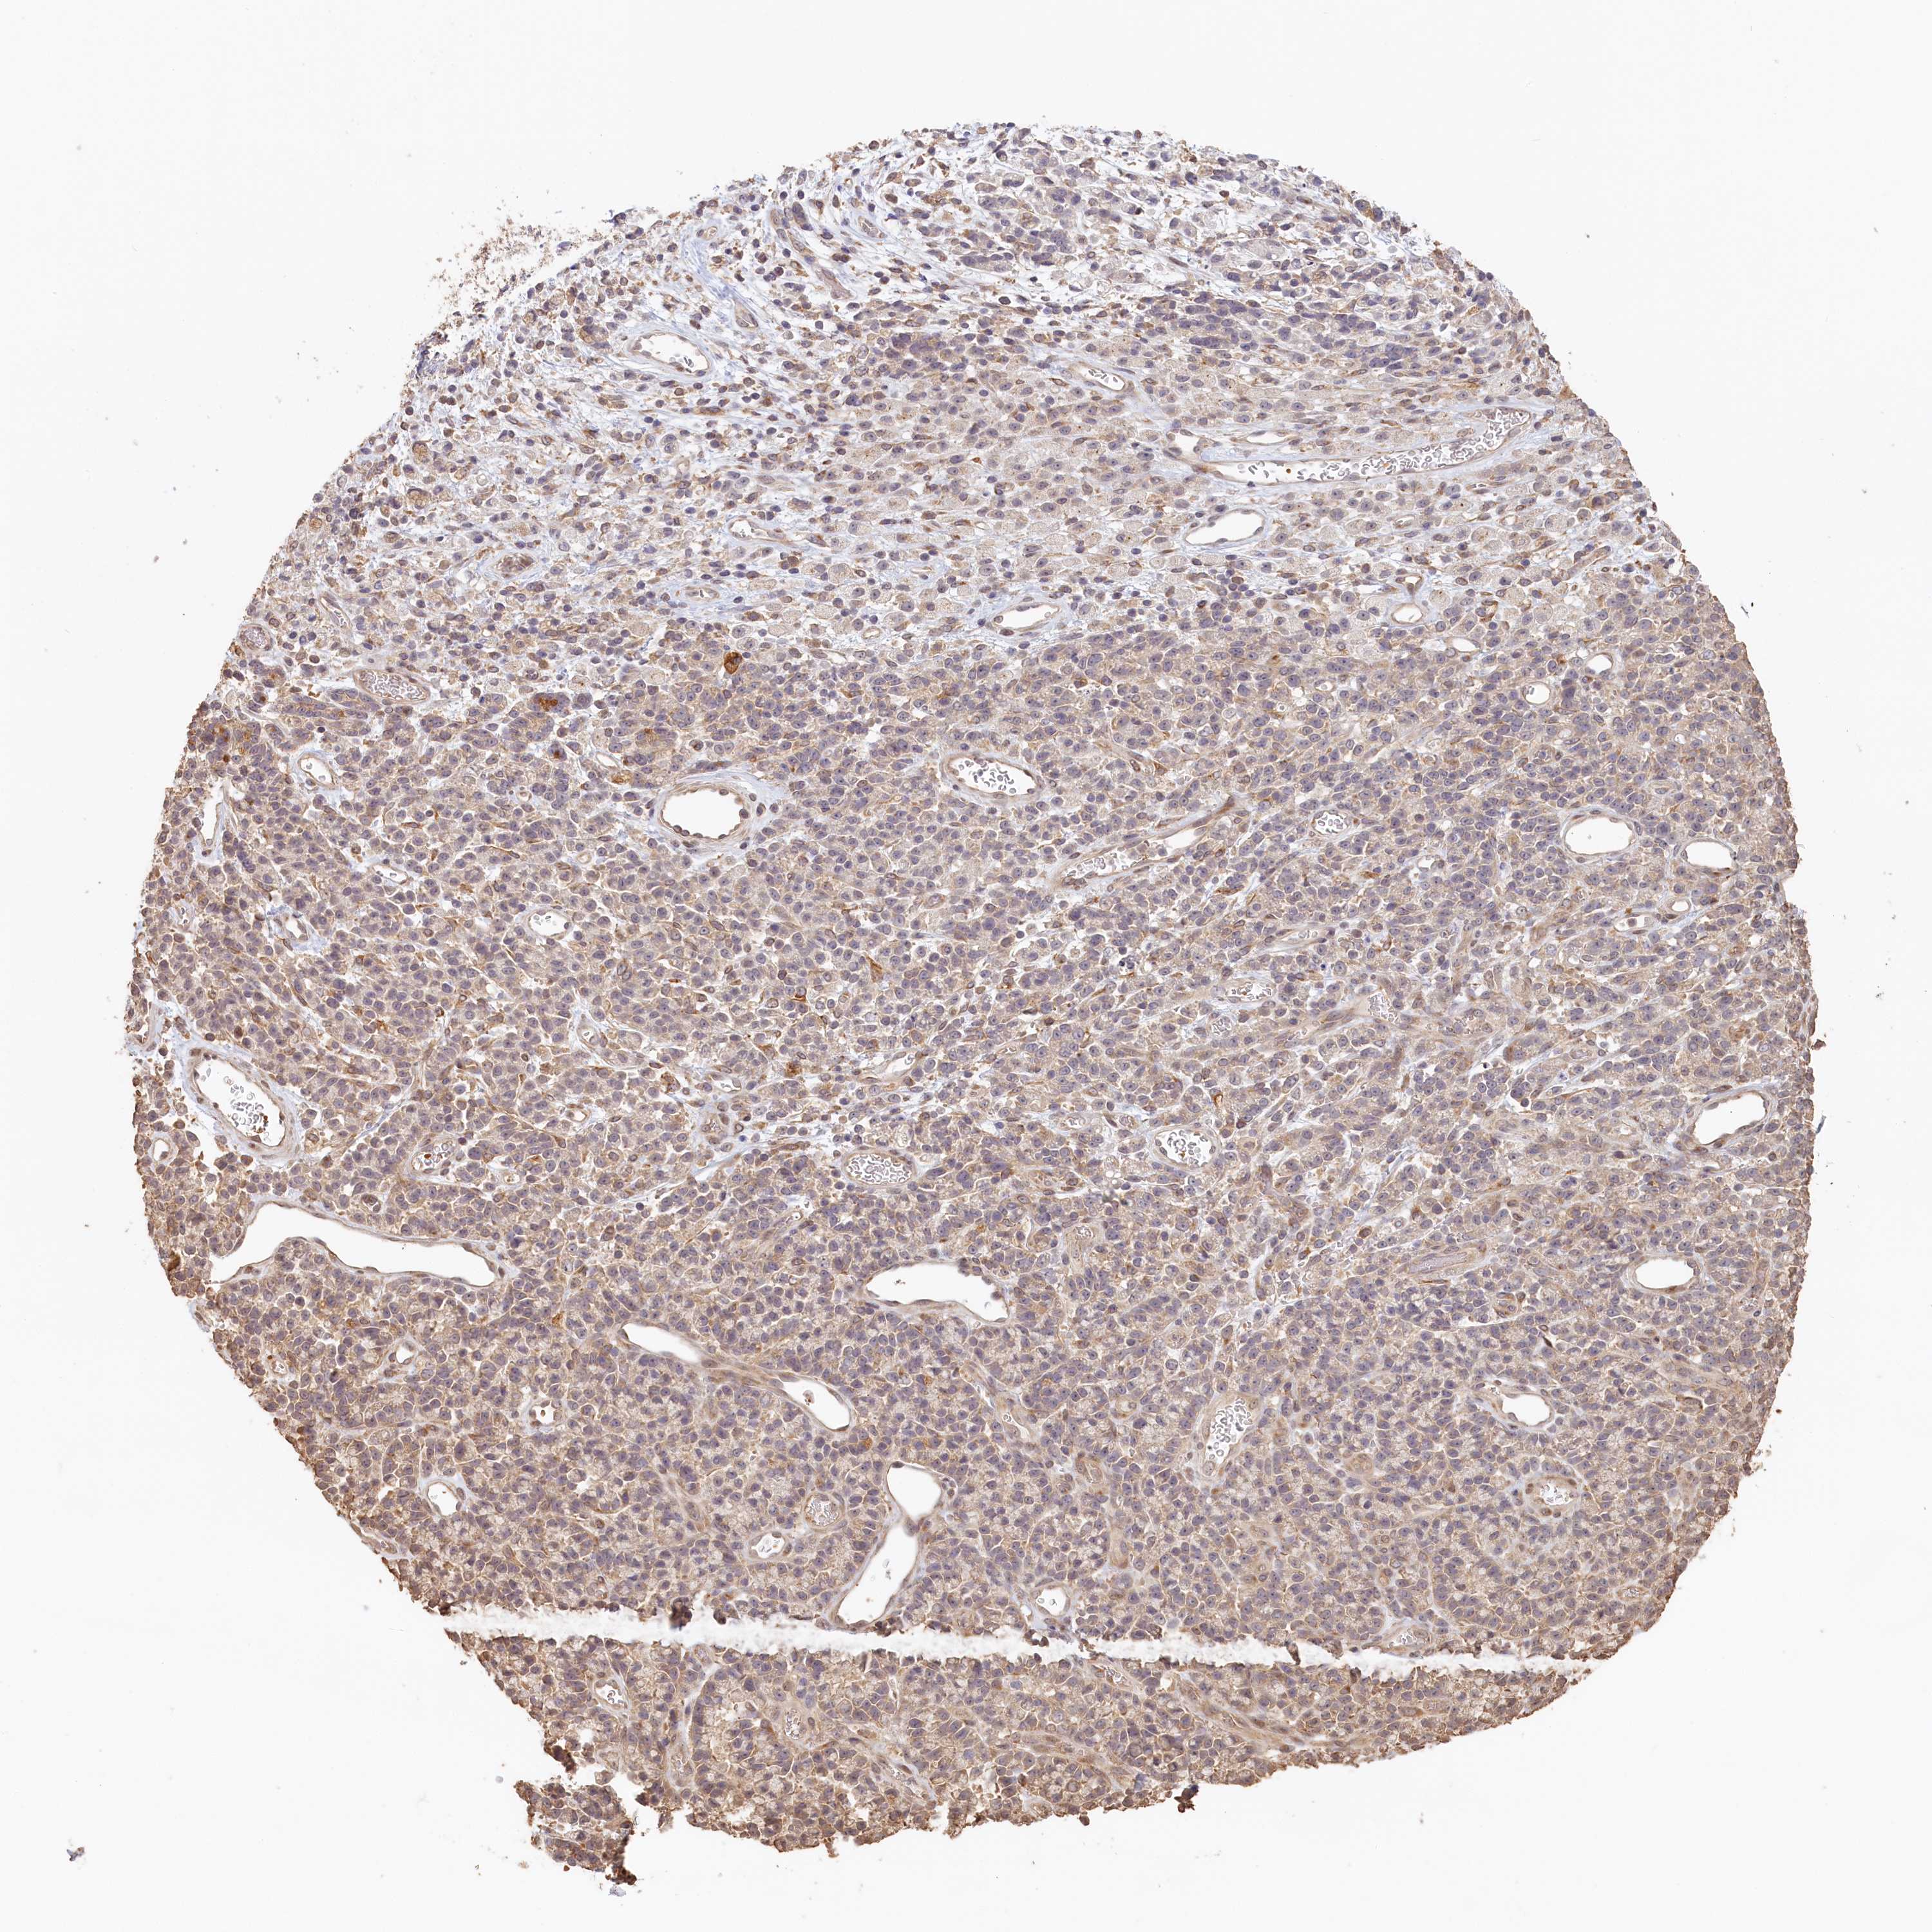

STOMACH CANCER - Protein expressioni

A mouse-over function shows sample information and annotation data. Click on an image to view it in a full screen mode. Samples can be filtered based on level of antibody staining by selecting one or several of the following categories: high, medium, low and not detected. The assay and annotation is described here.

Note that samples used for immunohistochemistry by the Human Protein Atlas do not correspond to samples in the TCGA dataset.

Antibody stainingi

Antibody staining in the annotated cell types in the current human tissue is reported as not detected, low, medium, or high, based on conventional immunohistochemistry profiling in selected tissues. This score is based on the combination of the staining intensity and fraction of stained cells.

Each image is clickable and will lead to virtual microscopy that enables deeper exploration of all samples and also displays staining intensity scores, fraction scores and subcellular localization as well as patient and tissue information for each sample.

Antibody HPA041019

Antibody HPA042033

Staining

High

Medium

Low

Not detected

Intensity

Strong

Moderate

Weak

Negative

Quantity

>75%

75%-25%

<25%

None

Location

Nuclear

Cytoplasmic/membranous

Cytoplasmic/membranous,nuclear

Adenocarcinoma, NOS